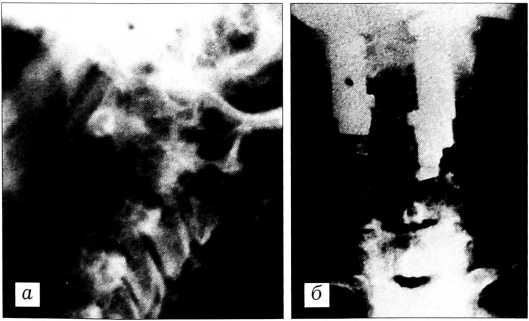

Костно-хрящевые экзостозы (солитарные или множественные) составляют 18,5%. Встречаются у лиц молодого возраста. Экзостоз исходит из элементов дуги. Клинически проявляется безболезненной припухлостью, спаянной с костью, может вызывать радикулярные боли и с течением времени быстро расти. В отличие от костно-хрящевого экзостоза длинных костей, у экзостоза позвоночника ножка более плотная, чем остальная часть. Иногда новообразование достигает больших размеров и имеет вид «цветной капусты» (рис. 1).

Рис. 1. Больная Б. 11 лет. Новообразование, исходящее из дуги L4 (а), распространяется от подвздошной кости до XI ребра (б), имеет вид «цветной капусты» (в). Новообразование удалено с частью дуги L4. Гистологическое исследование: костно-хрящевой экзостоз.